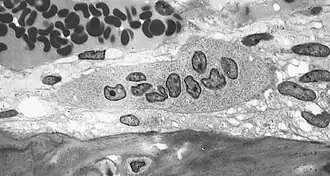

El osteoclasto es una célula multinucleada, móvil y gigante que degrada, reabsorbe y remodela huesos. Al igual que el osteoblasto, está implicado en la remodelación del hueso natural. Deriva de células hematológicas. Los osteoclastos, células responsables de la reabsorción de la matriz ósea, son células acidófilas y polinucleadas de gran tamaño. Ocupan una cavidad llamada laguna de resorción o laguna de Howship y se localizan en las superficies óseas firmemente asociadas a la matriz ósea, por medio de integrinas (α5β3). Los osteoclastos se forman por la fusión de varias células mononucleares derivadas de una célula madre sanguínea de la médula ósea, mostrando muchas propiedades de los macrófagos, formando parte del sistema monocítico macrofágico.

Los osteoclastos se caracterizan por poseer una porción de su membrana "arrugada", en forma de cepillo, rodeada de un citoplasma libre de orgánulos llamada "zona clara", con la que se adhiere a la superficie del hueso mediante integrinas, unos receptores especializados del hueso. El proceso de resorción se inicia cuando el aparato de MRD de las células excreta lisosomas con enzimas capaces de producir un microambiente ácido por debajo de la membrana arrugada como consecuencia del transporte de protones mediante la bomba de protones ATP-dependiente, el intercambio Na+/H+ y la anhidrasa carbónica. Las enzimas lisosomales de los osteoclastos implicadas en este proceso son cistein-proteasas como la catepsina y sobre todo, la fosfatasa ácida tartrato-resistente (esta última se utiliza como marcador del fenotipo osteoclástico). Las enzimas lisosomales solo son liberadas en la zona clara en las proximidades del borde arrugado produciéndose en esta área las reacciones de degradación de la matriz que deben producirse antes de que el medio ácido disuelva las sales minerales del hueso.